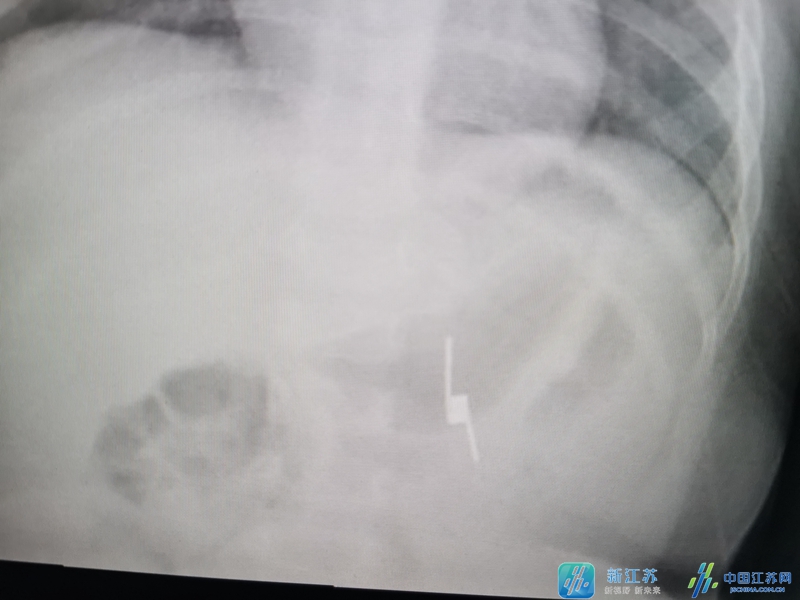

新江苏·中国江苏网讯 (记者 孙骏 通讯员 张国强)“是一个两头尖的发夹弹簧,按照X片的定位,正在胃里面”,当南京医科大学第二附属医院儿童消化内科盛伟松主任把这个情况告诉黄师傅时,黄师傅顿时紧张起来。

接诊的医生儿童消化科盛伟松主任检查后发现,在这个7个月大的婴儿的胃里赫然有一个发夹弹簧。“现在该怎么办?”黄师傅夫妻焦急的问盛主任。“如不及时取出,两头尖尖的弹簧会穿破胃肠道,到时就需要外科手术治疗了,目前最好的办法是通过胃镜取出来。”盛主任建议对婴儿施行全身麻醉的急诊胃镜来取异物,黄师傅和妻子商量后表示同意,随后小宝宝被安排进入儿童胃镜室。医生护士相互配合,密切关注婴儿病情变化。由于弹簧两头是尖尖的钢丝,医生小心翼翼的将内镜夹住缓缓的退出,成功取出了食道异物,手术过程十分顺利,婴儿平安返回病房。